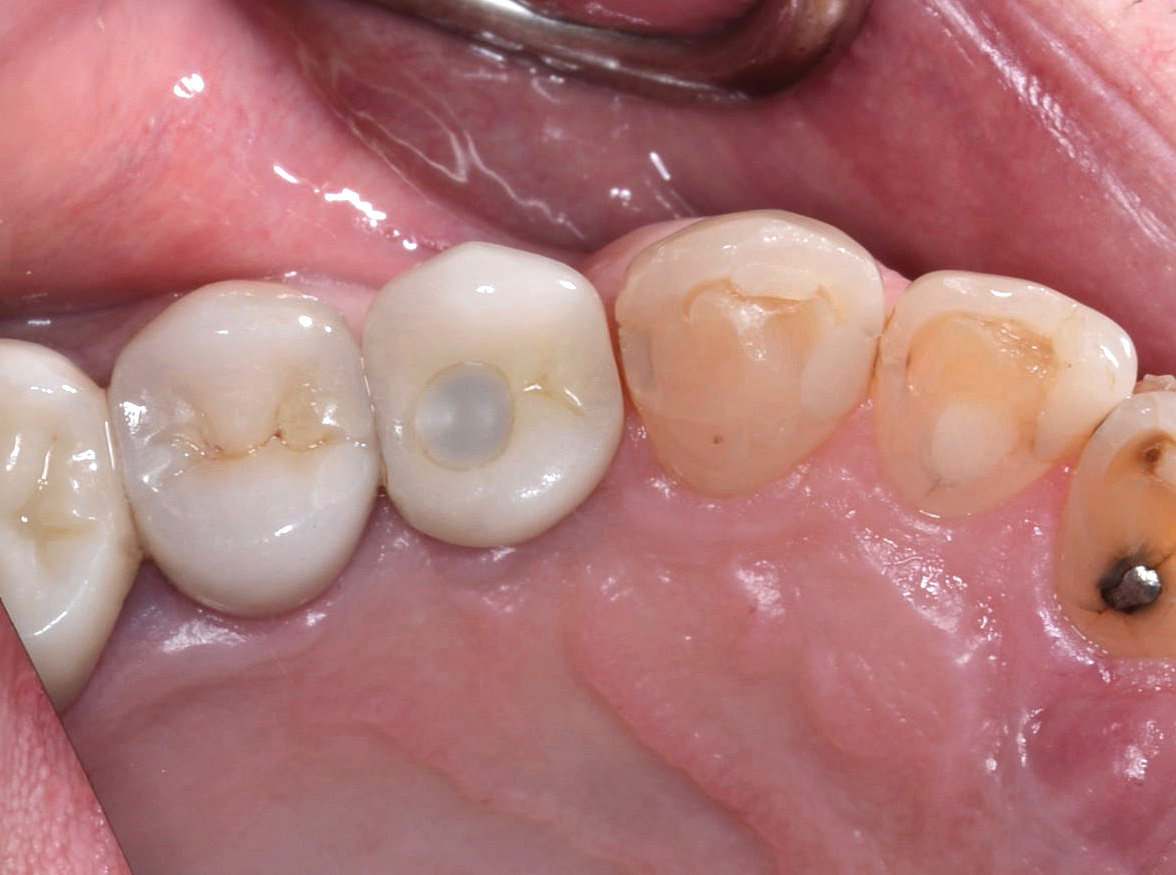

Fig 8. Loss of restoration and subsequent tissue overgrowth from broken abutment screw as shown in the radiograph (Fig 9).

Figure 8

Fig 9. Radiograph depicting fractured screw inside of the implant.

Figure 9